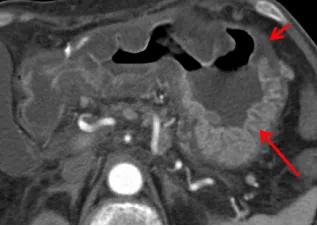

75 岁男性,急性胃炎,恶性呕吐就诊。CT 增强示胃壁弥漫性增厚,粘膜明显强化,可见粘膜下水肿。

中年女性,因坐骨神经痛使用强的松治疗后出现恶心。冠状位 CT 示胃窦部偏心性增厚及粘膜下水肿,胃体部正常。内镜活检证实为急性胃炎。